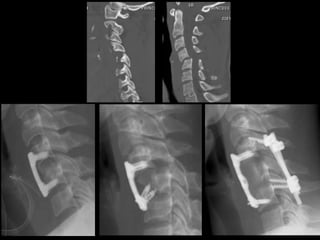

Surgery

• anterior approach

– discectomy, graft and fusion

– better tolerated

– can directly remove disc

– proven to be clinically effective

• posterior approach

– lateral mass fusion

– operation directed at pathology

– more biomechanically sound

– allows direct facet reduction